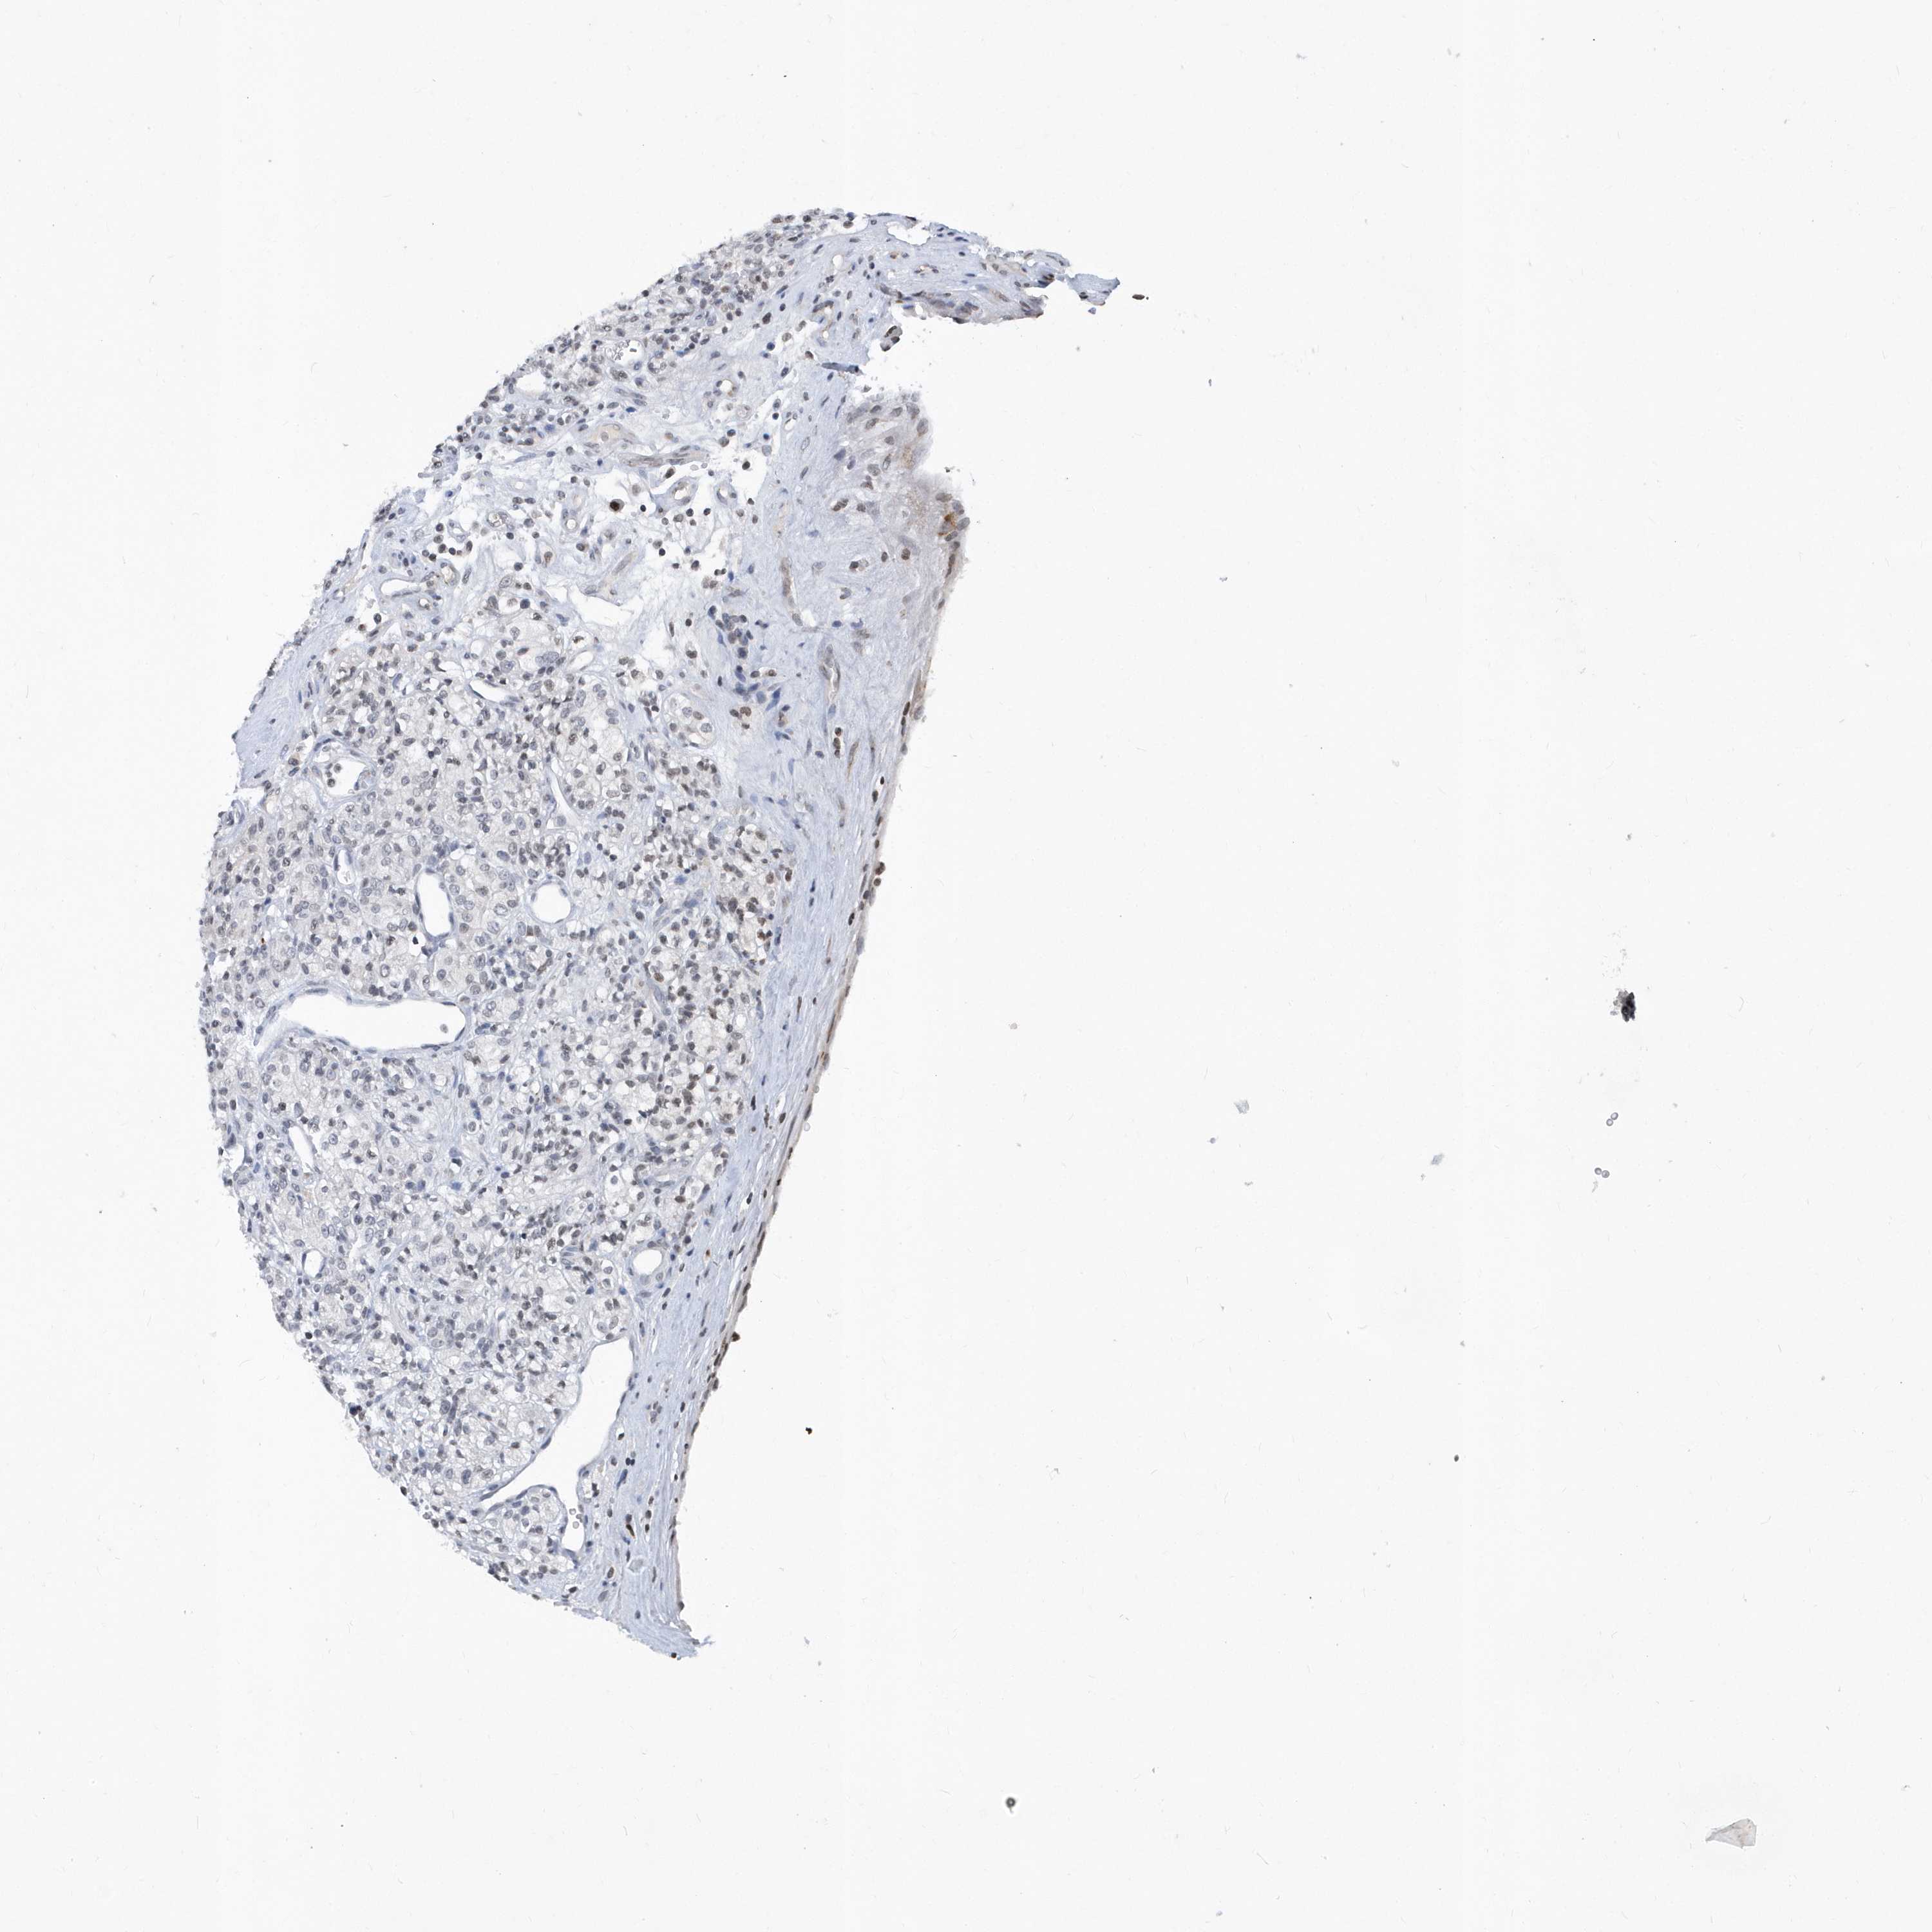

KIDNEY RENAL CLEAR CELL CARCINOMA (VALIDATION) - Interactive survival scatter ploti

The Survival Scatter plot shows the clinical status (i.e. dead or alive) for all individuals in the patient cohort, based on the same data that underlies the corresponding Kaplan-Meier plots. Patients that are alive at last time for follow-up are shown in blue and patients who have died during the study are shown in red.

The x-axis shows the expression levels (FPKM) of the investigated gene in the tumor tissue at the time of diagnosis. The y-axis shows the follow-up time after diagnosis (years). Both axes are complimented with kernel density curves demonstrating the data density over the axes. The top density plot shows the expression levels (FPKM) distribution among dead (red) and alive patients (blue). The right density plot shows the data density of the survived years of dead patients with high and low expression levels respectively, stratified using the cutoff indicated by the vertical dashed line through the Survival Scatter plot. This cutoff is automatically defined based on the FPKM cutoff that minimizes the p-score. The cutoff can be changed by dragging the vertical line or by entering a cutoff value in the square labeled "Current cut-off".

Under the Survival Scatter plot the p-score landscape (black curve; left axis) is shown together with dead median separation (red curve; right axis). Dead median separation is the difference in median mRNA expression between patients who have died with high and low expression, respectively. It is calculated as follows: median FPKM expression of dead patients with high expression - median FPKM expression of dead patients with low expression. This is intended to aid the user in visually exploring custom cutoffs and the associated p-scores and dead median separation.

Individual patient data is displayed and can be filtered by clicking on one or more of the category buttons on the top of the page. Categories describing expression level and patient information include: high, low, alive, dead, female, male and tumor stages. The scale of the x-axis can be toggled between linear and log-scale by clicking on the "x log" button. Mouse-over function shows TCGA ID, patient information and mRNA expression (FPKM) for each patient.

& Survival analysisi

Kaplan-Meier plots summarize results from analysis of correlation between mRNA expression level and patient survival. Patients were divided based on level of expression into one of the two groups "low" (under cut off) or "high" (over cut off). X-axis shows time for survival (years) and y-axis shows the probability of survival, where 1.0 corresponds to 100 percent.

VWA5B2 is not prognostic in Kidney Renal Clear Cell Carcinoma (validation)

: N/A

N/A